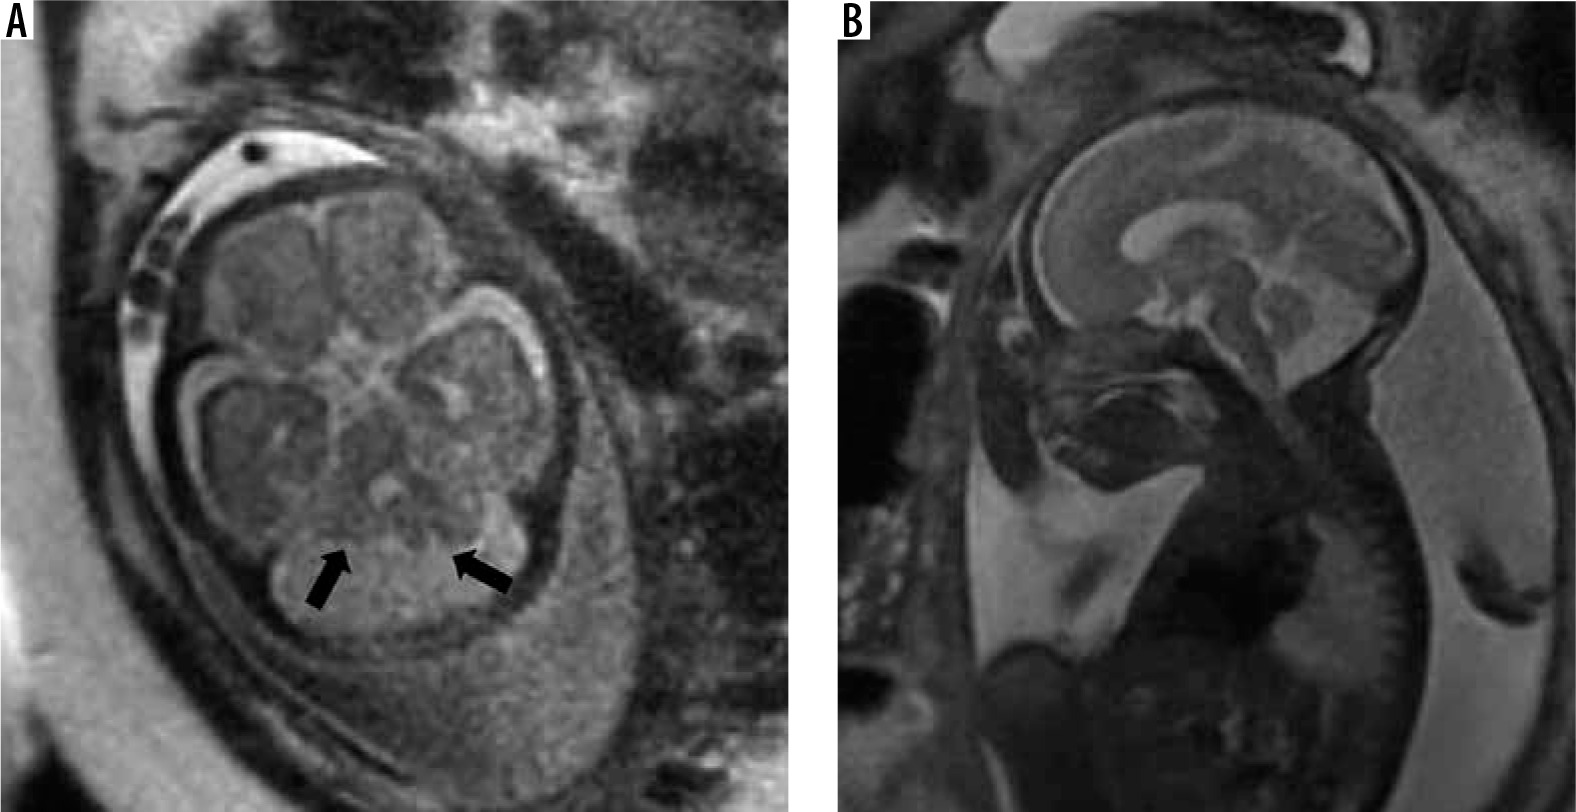

Kinked/z-shaped brainstem

This is a rare anomaly caused by arrested brainstem development at around 7 weeks of gestational age, with resultant abnormal persistence of brainstem flexures (Figure 16). It can be seen in congenital muscular dystrophies, tubulinopathies, and X-linked hydrocephalus. Unlike the brainstem-predominant malformations described earlier, kinked brainstem is almost always accompanied by other anomalies such as ventriculomegaly, cerebellar hypoplasia, neuronal migration disorders, or corpus callosal dysgenesis. Neurodevelopmental outcome is usually very poor [29,30].

Figure 16

Z-shaped brainstem – gestation age 21 weeks – sagittal (A) T2w HASTE image shows small vermis and abnormal Z-shaped morphology of the brainstem due to kinking (arrow). Axial (B) T2w HASTE image through the posterior fossa shows hypoplastic cerebellum. C) Axial T2w HASTE image through the lateral ventricles shows ventriculomegaly. Termination of pregnancy was done